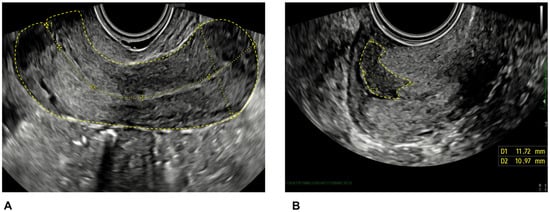

Tumor size was measured in three orthogonal diameters (craniocaudal, transverse, and anteroposterior). The craniocaudal extension was measured in a longitudinal section from the outermost margin of the tumor (facing the vagina) to the highest (most cranial) extension of the tumor (Figure 1), and the anteroposterior extension was measured perpendicular to this measurement. The transverse extension was measured in the transverse section between the outermost lateral margins of the tumor. The tumor volume was calculated with the formula of a sphere, Tvol = D1 × D2 × D3 × 0.53. Tumor echogenicity was classified as hypoechoic, isoechoic, hyperechoic, or mixed compared with the surrounding cervical tissue.

Figure 1.

Ultrasound scan image showing the uterus (A) and tumor (B) diameters in two dimensions.